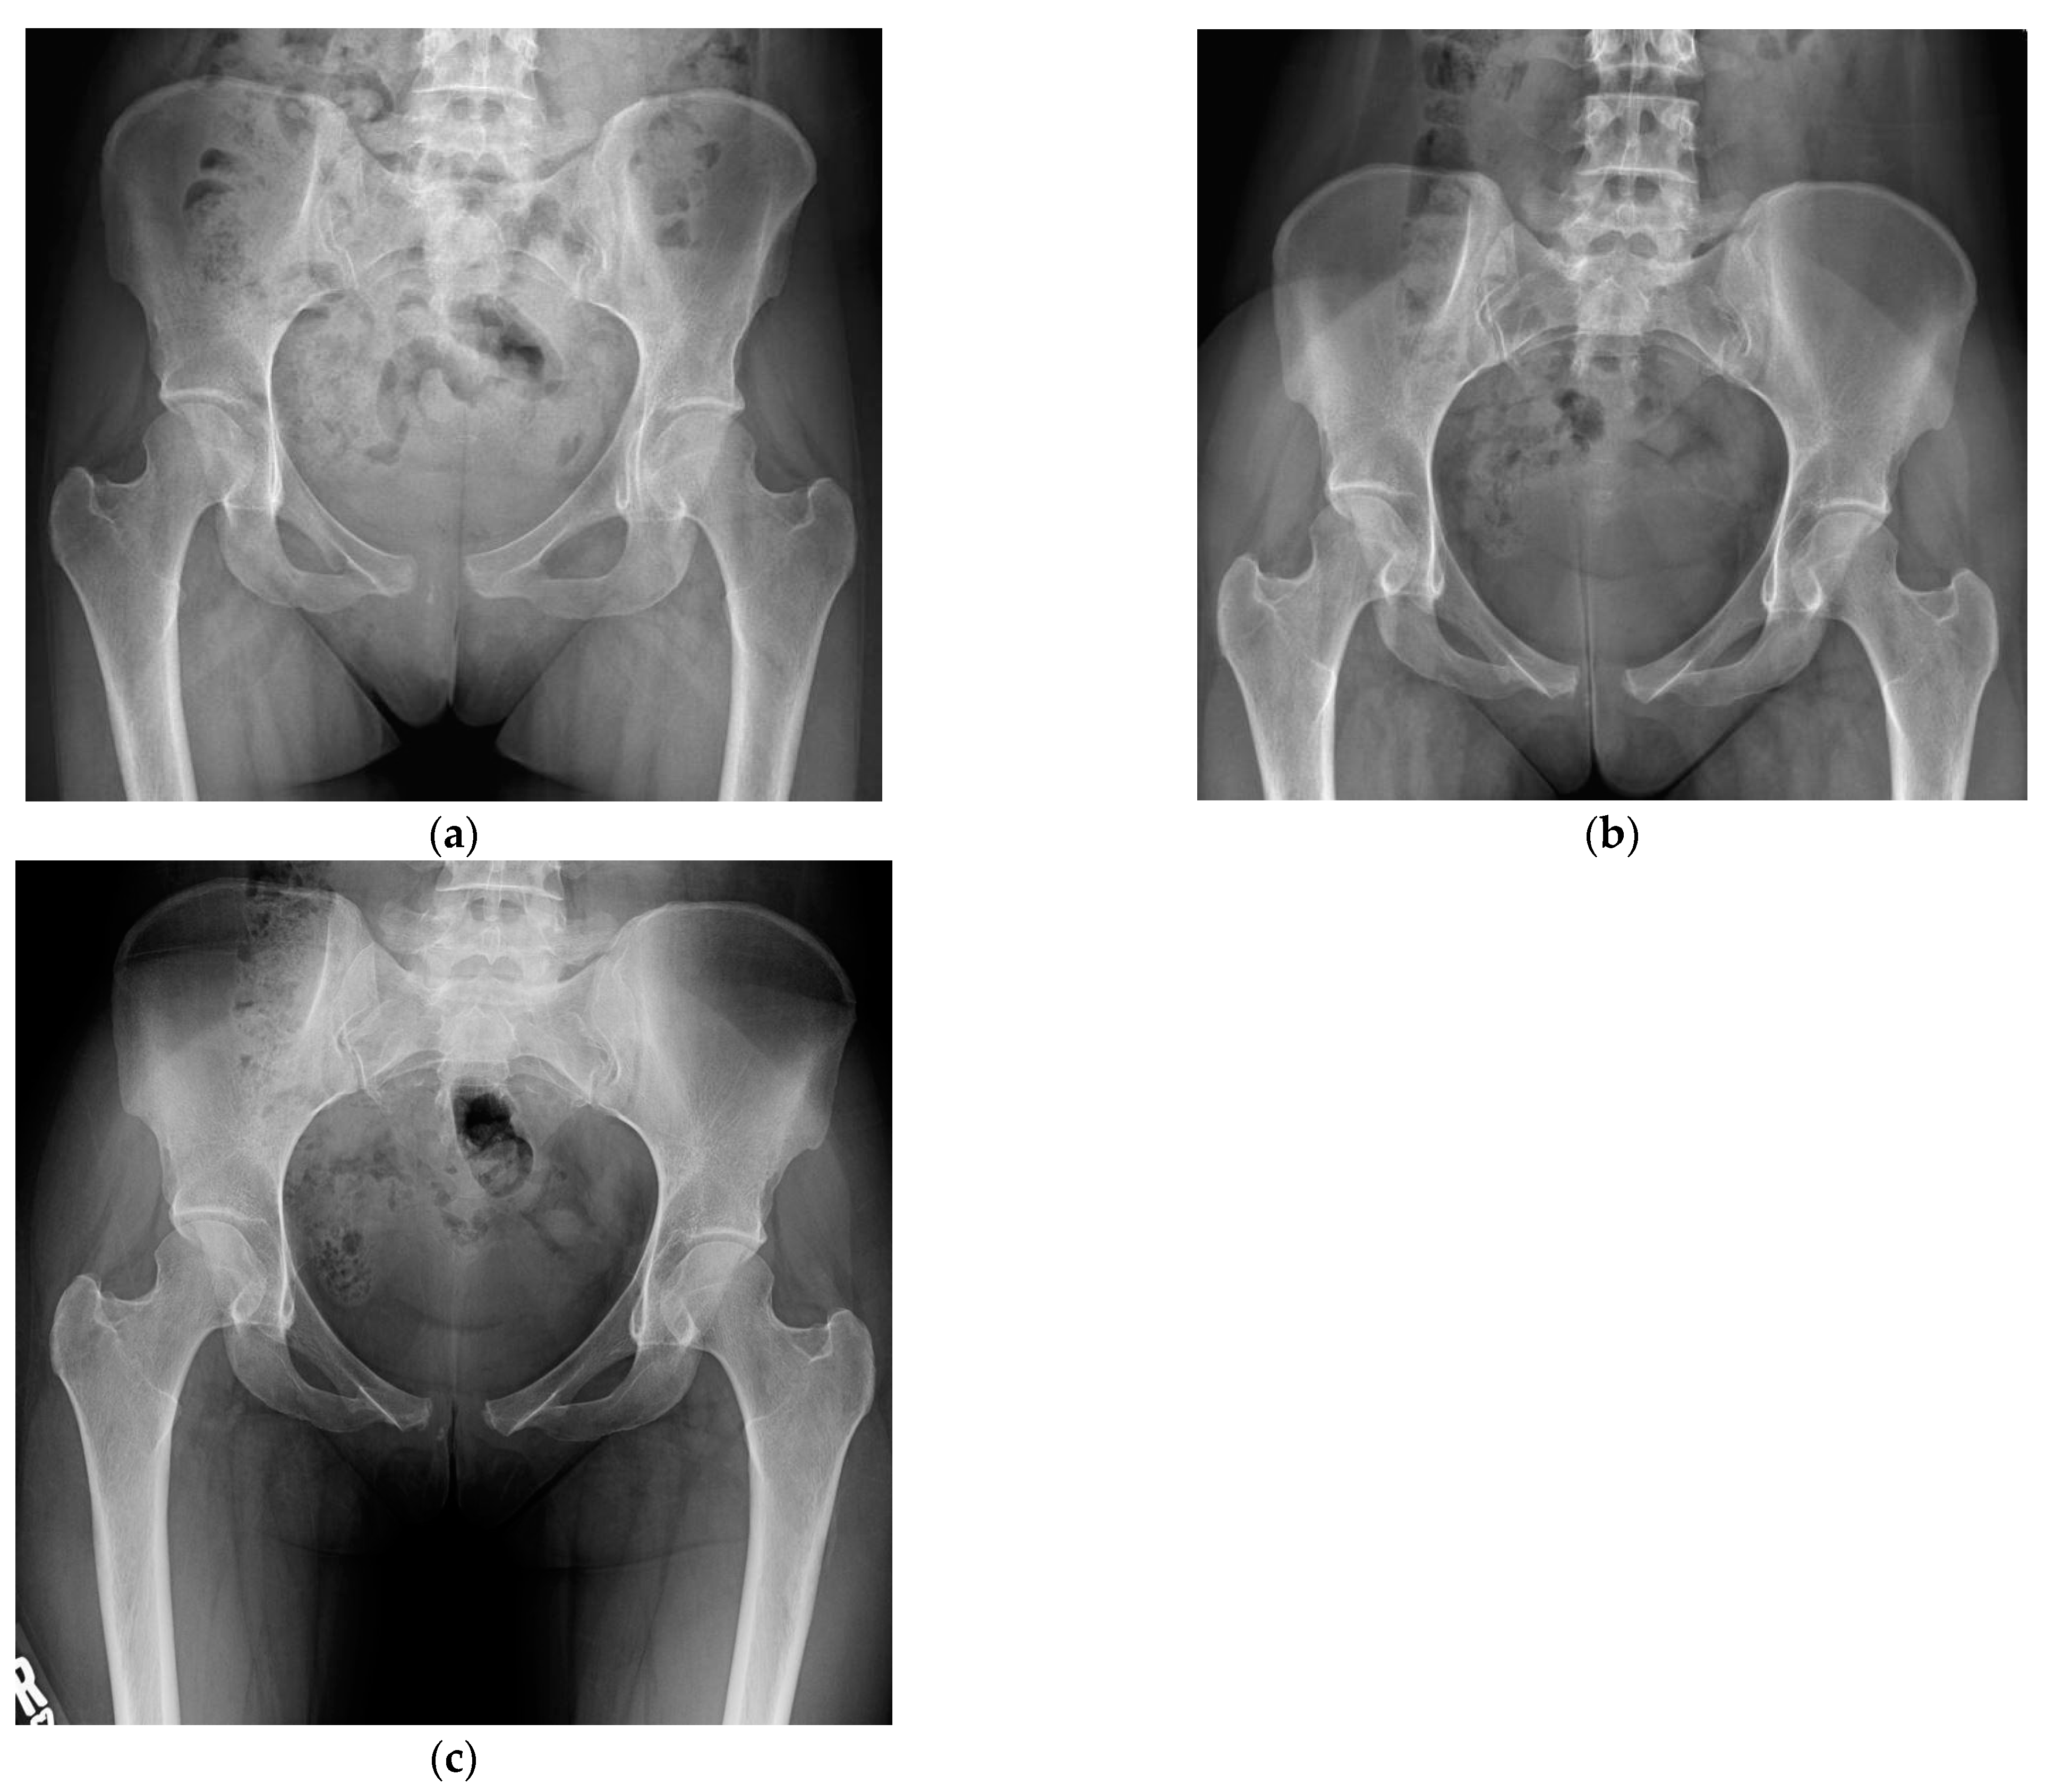

On hospital day five, the patient was hemodynamically stable with sufficient pain control, and she was discharged home with instructions to wear her binder as much as possible, aside from hygiene activities, and to limit her activities to avoid running, jumping, prolonged walking, and high-impact activities. At 3 weeks post-injury, pelvic radiographs demonstrated largely maintained alignment of the pubic symphysis with some mild increase in diastasis to 1.9 cm, and her pain was well managed via acetaminophen taken only at night (Figure 3). She was instructed to wean her binder use gradually beginning at 6 weeks post-injury. At 3 months post-injury, her pain had resolved, and her pelvic imaging continued to show maintained alignment at 1.9 cm(Figure 3). She was advanced to activity as tolerated. At her six-month follow-up, she was ambulating without restriction, including running, jumping, and playing competitive sports, with radiographic diastasis again measuring 1.9 cm (Figure 3).

Figure 3. Follow-up AP pelvis radiographs (a) 3-week post-injury AP pelvis radiograph; (b) 3-month post-injury AP pelvis radiograph; (c) 6-month post-injury AP pelvis radiograph.